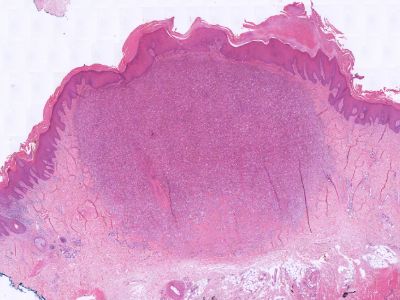

PA:Onder een acanthotische epidermis ziet men irregulaire, spitse papilvorming en woekering van jong, soms basofiel bindweefsel. Er is geen fraaie bundelvorming van het collageen, maar men ziet geïsoleerde vezels in een warrig patroon, soms loodrecht op de epidermis overgang verlopend. Aan de rand is er een geleidelijke overgang in normaal bindweefsel. Het elastine is afgenomen. Het fibroma is zeer rijk aan spoelvormige fibroblasten, soms echter overheersen histiocytaire cellen die ijzer en/of hemosiderine hebben gefagocyteerd (vandaar de naam 'histiocytoma'). Vaak ook zijn er mengvormen met talrijke fibroblasten en histiocyten. Ook vet komt er veel in voor. Deze cellen en hun inhoud (vet en/of ijzer) bepalen de kleurvarianten. Een enkele keer gaan de histiocyten in schimachtige reuzencellen over en lijken ze op Touton cellen (zie xanthomen). Soms is er een beduidende nieuwvorming van capillairen.

Zie ook de

ingescande PA-coupe van de

afdeling pathologie van de University of

Toronto.